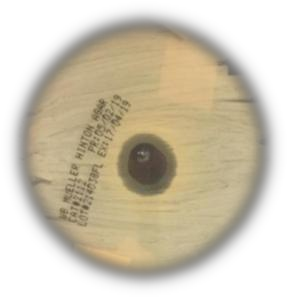

Table 3: The images of the inhibition zone of different musk 25% concentration on microbes

| N. M. | B. M. | W. M. | |

| B. subtilis | ![]() |

![]() |